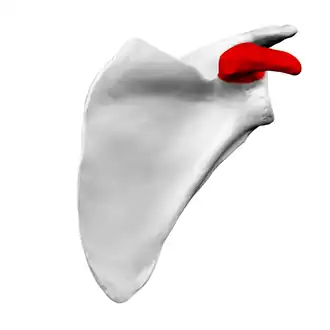

Left scapula. Anterior view. Coracoid process shown in red. | |

Anterior view. Coracoid process shown in red. | |

The coracoid process (from Greek κόραξ, raven[1]) is a small hook-like structure on the lateral edge of the superior anterior portion of the scapula (hence: coracoid, or "like a raven's beak"). Pointing laterally forward, it, together with the acromion, serves to stabilize the shoulder joint. It is palpable in the deltopectoral groove between the deltoid and pectoralis major muscles.

Left scapula. Coracoid process shown in red.

Left scapula. Coracoid process shown in red. -